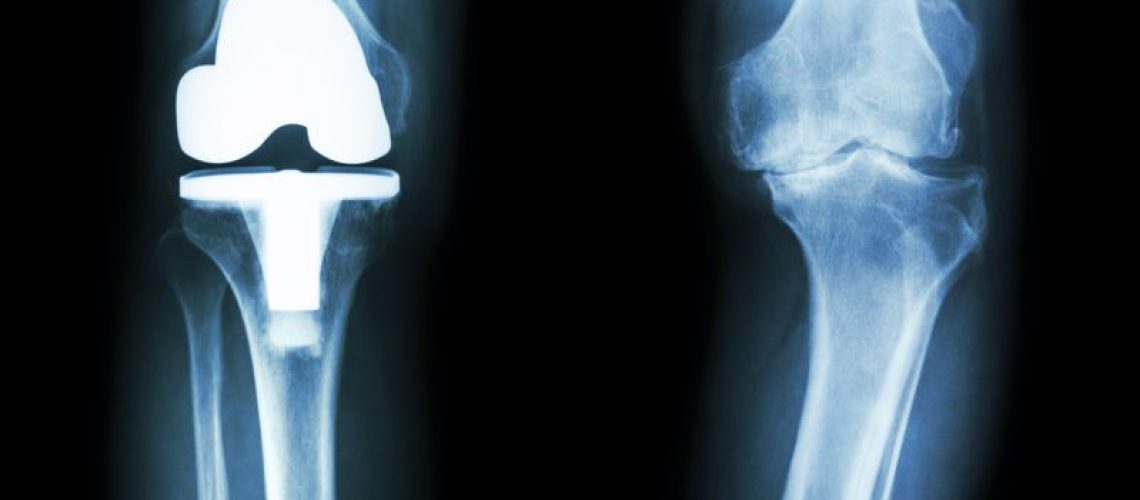

Também chamada de artroplastia, a retirada de uma parte doente da articulação do osso para substituição por uma prótese de joelho, é uma forma de restabelecer a sustentação muscular e os movimentos do corpo nessa área. Ela é usada quando há incidência de qualquer doença que atinja a área operada e possa inibir o paciente na movimentação.

No caso da colocação da prótese de joelho, o cirurgião inicia o procedimento cirúrgico logo após a anestesia surtir efeito no paciente. As partes danificadas da articulação do osso são serradas e substituídas por essa prótese, que pode ser de metal ou mesmo de plástico. Ela é moldada de forma a se encaixar perfeitamente no osso do paciente e, assim, restaurar os movimentos e as funções do joelho.

Para tanto, muitos metais são também utilizados, tais como aço inoxidável, titânio e cromo. Já o material plástico, por sua vez, é de polietileno, sendo durável e resistente a qualquer desgaste.